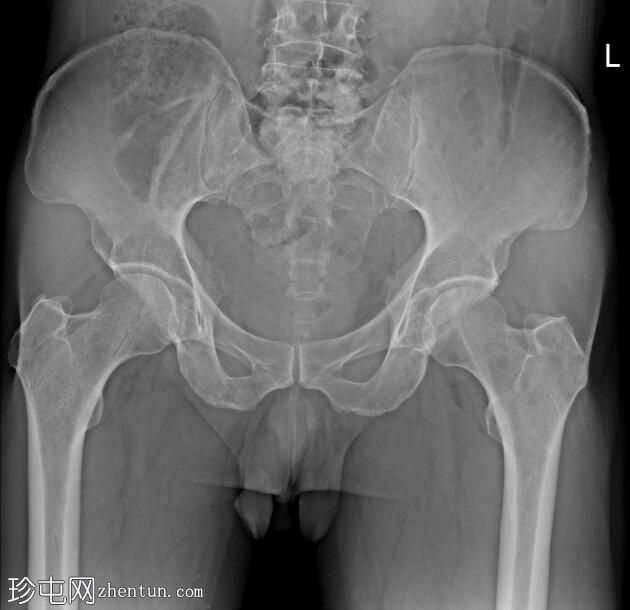

正位

斜位

前列腺部、膜部、球部及阴茎部尿道均正常。

造影剂经尿道注入,开始充盈具有肠袢特征的新膀胱。

该患者确诊为移行细胞癌后行膀胱切除术。治疗方案包括根治性膀胱切除术及新膀胱重建术。